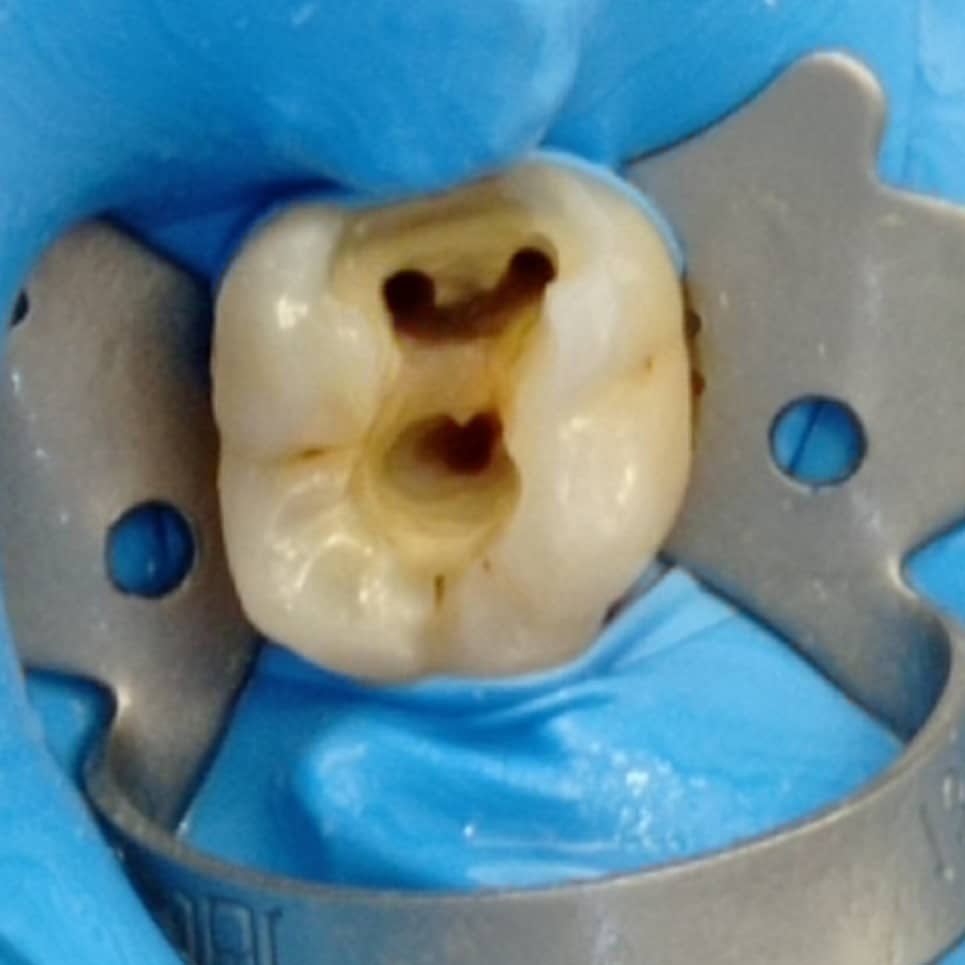

Η απονεύρωση, γίνεται όταν πλέον το δόντι έχει νεκρωθεί για κάποιο λόγο, βλέπε φλεγμονή, κάταγμα, εκτεταμένη τερηδόνα, είτε γιατί έχει σπάσει αρκετά και πρέπει στα πλαίσια της αναπλήρωσης του και αποκατάστασης να απονευρωθεί για να διατηρηθεί σωστά στο στόμα μας, είτε γιατί έχει κάποια κύστη.

Είμαστε εξειδικευμένοι ~ με ετήσια μετεκπαίδευση στον τομέα των απονευρώσεων ~ και πραγματοποιούμε τις θεραπείες μας, με όλα τα τελευταία μέσα και τεχνολογία, πλήρως εναρμονισμένοι, ενημερωμένοι, για το μέγιστο άρτιο αποτέλεσμα.